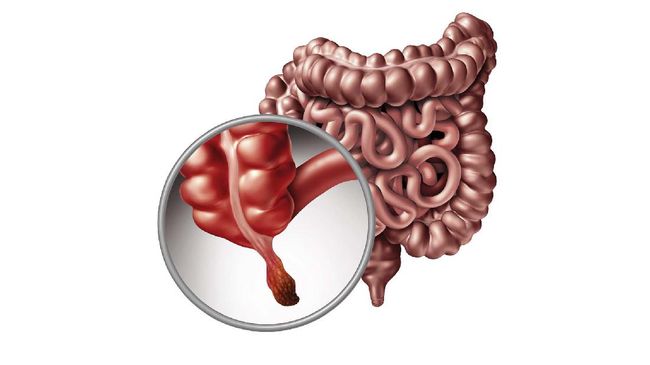

Penyebab Radang Usus Serta Gejalanya Yang Harus Diwaspadai Cegah Secepat Mungkin Merdeka Com

Penyebab Radang Usus Serta Gejalanya Yang Harus Diwaspadai Cegah Secepat Mungkin Merdeka Com